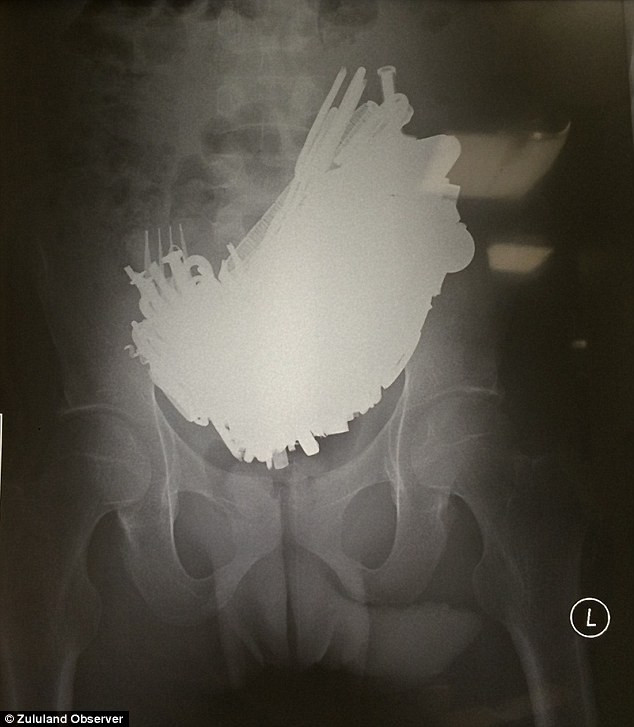

Peste 220 de obiecte au fost extrase din stomacul unui barbat din Africa de Sud. Boala rara de care sufera

Marti 09 Iunie 2015

Medicii din Africa de Sud au avut parte de unul dintre cele mai bizare cazuri cu care ...